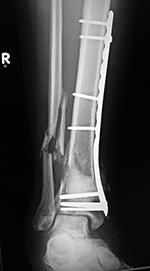

43 year-old man with comminuted right tibia and fibula fractures as well as extensive bone loss and soft tissue injury. A tibial intramedullary nail with proximal and distal locking screws is present as well as multiple rounded bony allografts. There are also large skin staples.